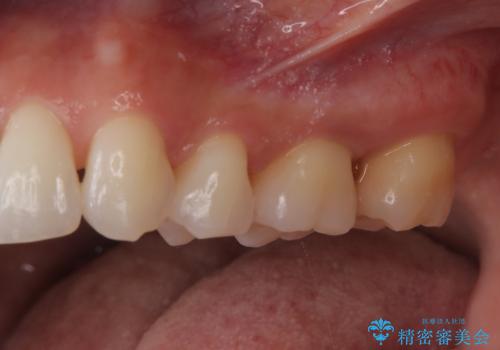

- 定期的にクリーニング(保険適応)に通って頂いている患者さんです。歯周ポケットが4ミリあったため歯茎を開いて歯石を除去するためにオープンフラップ術を行うことにしました。

歯周ポケットがそれほど深くない患者さんでしたが、いざ歯茎を開いてみるとそこにはたくさんの歯石がありました。もし歯周ポケットが4ミリだからと言って放置していれば数年後には、沢山の骨が無くなっていたことが予期出来ます。現段階で歯茎の下にある歯石を除去することにより骨が無くなることを予防する事が出来ました。